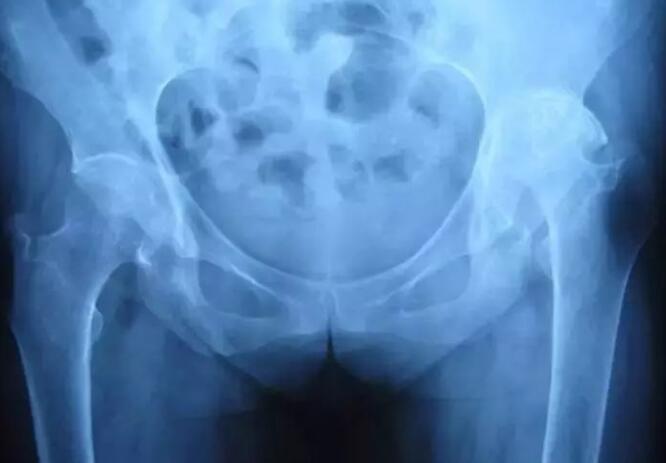

强直性脊柱炎是一种主要累及中轴骨胳的慢性炎症性疾病,主要侵犯骶髂关节、脊柱骨突、脊柱旁软组织及外周关节,并可伴发关节外表现。 临床主要表现为腰、背、颈、臀、髋部疼痛以及关节肿痛,严重者可发生脊...[详细]